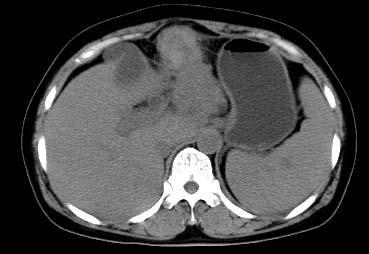

以下是引用西北一只狼在2008-6-30 20:58:00的发言:[br]肝左叶胆管细胞ca并肝门淋巴结转移、胰腺、胃小弯浸润

以下是引用ydx_74在2008-6-30 21:54:00的发言:[br]左叶胆管细胞ca并肝门淋巴结转移、胰腺、胃小弯浸润